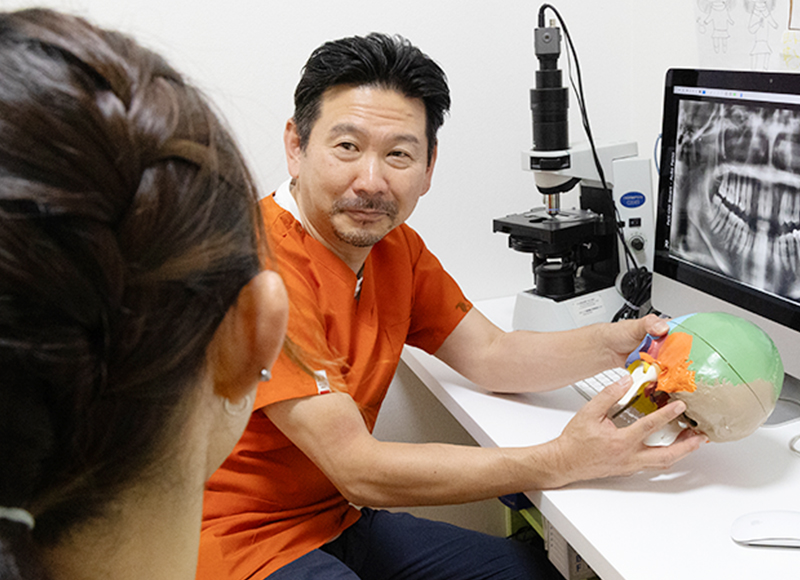

しかし、虫歯の発見が遅く進行してしまっていると、やはり多く削ったり神経を抜いたりしなければならなくなります。複雑な形状をした歯、中でも歯の根を治療する際に、できるだけ少ない処置で患部を取り残さないようにするため、当院では拡大鏡を使用しています。肉眼では確認できない細部まで見て、緻密な作業ができることが魅力です。

当院では、患者さまに細菌の種類や数が分かるだ液検査をおすすめしています。歯周病を引き起こす細菌は複数あり、その種類によっておすすめの治療方法や口臭のリスクが異なるからです。治療後の変化も確認できますので、治療のモチベーション維持に役立ててはいかがでしょうか。

検査には歯科用CTを用い、マウスピースや矯正によって治療します。お口の健康作りとお口に原因がある不調の改善で、当院がお役に立てたらと思います。